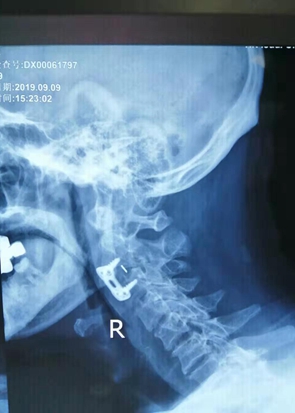

9月4日上午,在刘院长、谢院长的指导下,以李主任为首的脊柱外科专业团队,在全麻下为彭大爷行“颈2椎体骨折脱位前路骨折复位、颈2∕3椎间盘摘除、cage植骨融合、自锁钛板内固定术、胸8椎体压缩性骨折经皮椎体成形术”。2小时后,手术顺利完成,术中出血不到30 ml。术后三天,彭大爷颈部、腰部疼痛消失,佩戴头颈胸外固定支架下床活动,个人生活能基本自理,患者及家属对在娄底市骨伤医院“花小钱、治大病”的治疗效果非常满意!